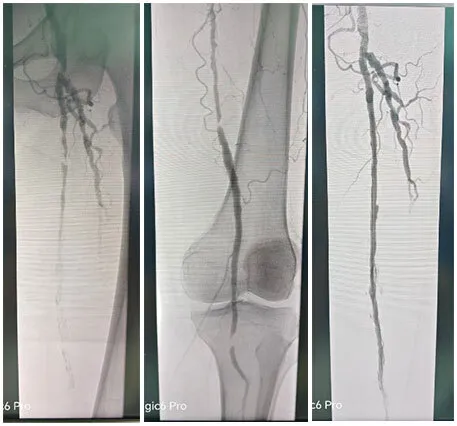

主诉åQ?/strong>åŒä¸‹è‚¢é—´æ­‡æ€§è·›è¡?òq?加é‡3月余ã€?/p>

术å‰è¯Šæ–­åQšå¤–院CTA½CÞZ¸‹è‚¢åŠ¨è„‰ç¡¬åŒ–é—­å¡žç—‡,åŒä¾§è†ä¸‹åŠ¨è„‰å¤šå‘多支下肢动脉闭塞ã€?/p>

手术˜q‡ç¨‹åQ?/strong>å¯ég¸å¯¼ç®¡é…åˆå»ºç«‹é€šèµ\åŽï¼Œä½¿ç”¨2.5*150mmã€?*120mmçƒå›Šæ‰©å¼ èƒ«åŽåŠ¨è„‰ç‹­çª„ŒDµï¼Œä½¿ç”¨2*80mmã€?.5*150mmçƒå›Šæ‰©å¼ è…“动脉狭½H„段åQŒé¢„扩åŽä½¿ç”¨¾U¦æŸåž‹è¯ç‰©çƒå›?*120mmã€?*150mm分别扩张胫åŽåŠ¨è„‰ã€è…“åŠ¨è„‰ã€‚å¤æŸ¥é€ åª„½Cºå†…膜光滑,无造媄剂外渗,è†ä¸‹˜qœç«¯åŠ¨è„‰ä¸¤æ”¯æ˜‘Öª„è‰¯å¥½ã€‚æ‰‹æœ¯é¡ºåˆ©ï¼Œæœ¯åŽæ‚£è€…安˜q”ç—…æˆÑ€?/p>

03 病例�/strong>

主诉åQ?/strong>åŒä¸‹è‚¢åŠ¨è„‰é—­å¡?月余åQŒå·¦ä¸‹è‚¢æœ¯åŽ3周余ã€?/p>

术å‰è¯Šæ–­åQ?/strong>下肢CTA½CºåŒä¸‹è‚¢åŠ¨è„‰å¤šå‘æ··åˆæ–‘å—åQŒç®¡è…”轻中度狭窄åQŒå·¦ä¾§è‚¡æ·±åŠ¨è„‰å¤šå‘æØœåˆæ–‘å—,½Ž¡è…”局部闭塞ã€?/p>

手术˜q‡ç¨‹åQ?/strong>å¯ég¸å¯¼ç®¡é…åˆå»ºç«‹é€šèµ\åŽï¼Œä¿æŠ¤ä¼žä¸‹ä½¿ç”¨4*150mmçƒå›Šé¢„扩张病å˜ï¼Œåˆ†åˆ«äº¤æ¢5*200mm¾U¦æŸåž‹è¯ç‰©çƒå›Šæ‰©å¼ é—­å¡žæ®µåŠè‚¡‹¹…动脉上ŒD늋­½H„处åQ?*150mm¾U¦æŸåž‹è¯ç‰©çƒå›Šæ‰©å¼ èƒ«è…“干开å£ä¸ŠŒDµï¼Œéž˜å†…造媄昄¡¤ºè‚¡æµ…å¼€å£å¤„有残余狭½H„,余闭塞段完全å¤é€šï¼Œå†…膜光整åQŒè¡€‹¹é€šç•…åQŒå¼•å…¥DES6*40m支架一枚予以股‹¹…å¼€å£å¤„释放åQŒå¤æŸ¥é€ åª„æç¤ºç‹­çª„解除åQŒæœªè§é€ åª„剂外渗,è†ä¸‹˜qœç«¯åŠ¨è„‰å„分支显å½Þp‰¯å¥½ï¼Œæœªè§æ˜Žæ˜¾æ “å¡žã€‚æ‰‹æœ¯é¡ºåˆ©ï¼Œæœ¯åŽæ‚£è€…安˜q”ç—…æˆÑ€?/p>